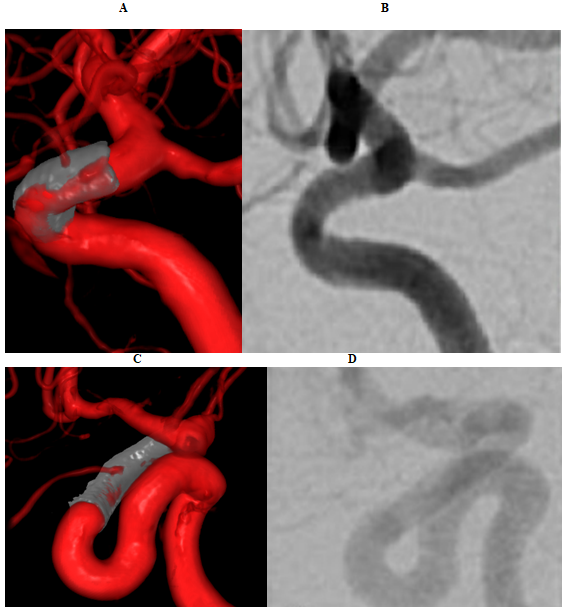

Figures 1 and 2 provided visual representation of aberrant neurovascular biomarkers in VR, which were quantified by minimal imaging important difference (Table 1) and NNI (Table 2). In NNI, CI included infinity with the exception of weighted stent stenosis in VR that had significant absolute risk reduction (11.76%, 95% CI 2.35-21.18). There were significant differences between unweighted and weighted minimal imaging important difference (test statistic t=3.70, P=0.006) and NNI (test statistic t=-2.29, P=0.05).

Figure 1 Biomarker detection in flow diversion. VR model of treated paraophthalmic aneurysm with endoleak (A) is not visualized on DSA (B). VR shows ophthalmic artery branch filling (C) not visualized on DSA (D).